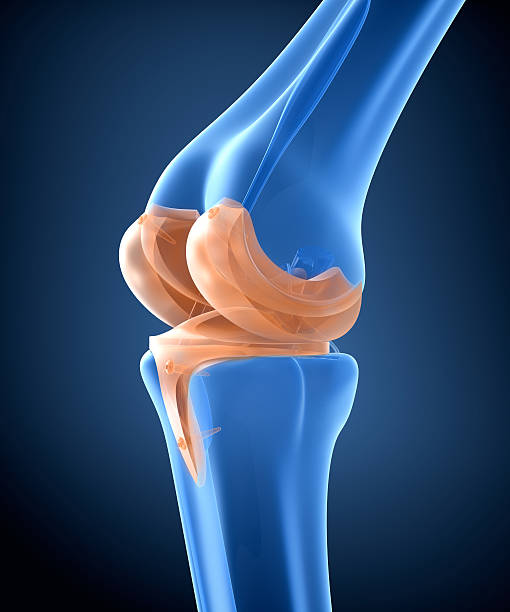

무릎 관절염에 의한 무릎 통증

무릎 관절염은 무릎 관절의 연골과 주변 조직들이 염증을 일으키는 질환으로, 노화, 과부하, 외상 등이 원인이 됩니다. 무릎 관절이 불안정해지고 염증이 발생하면 통증, 부종, 관절 강직 등의 증상이 나타납니다. 운동, 체중 감량, 약물 치료 등이 치료 방법으로 사용됩니다. 특히 중증도가 높은 경우 수술 치료가 필요할 수 있습니다.